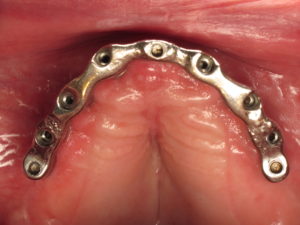

Il faut donc dans presque tous les cas de prothèse amovible complète au maxillaire donner la préférence à une option de barre, laquelle sera préférentiellement supportée par un minimum de quatre implants afin de consolider l’ancrage global.

Il est par ailleurs important dans le cas d’une barre réduite au secteur antérieur de conserver un appui palatin de la prothèse afin d’avoir une sustentation verticale plus efficace et de diminuer les stress mécaniques sur la barre antérieure en cas de pressions importantes au niveau des molaires (photo de gauche).

Si la barre est étendue sur toute l’arcade (photo de droite) le palais pourra alors être supprimé car la prothèse sera totalement implanto-portée.

- barre sur 4 implants au maxillaire